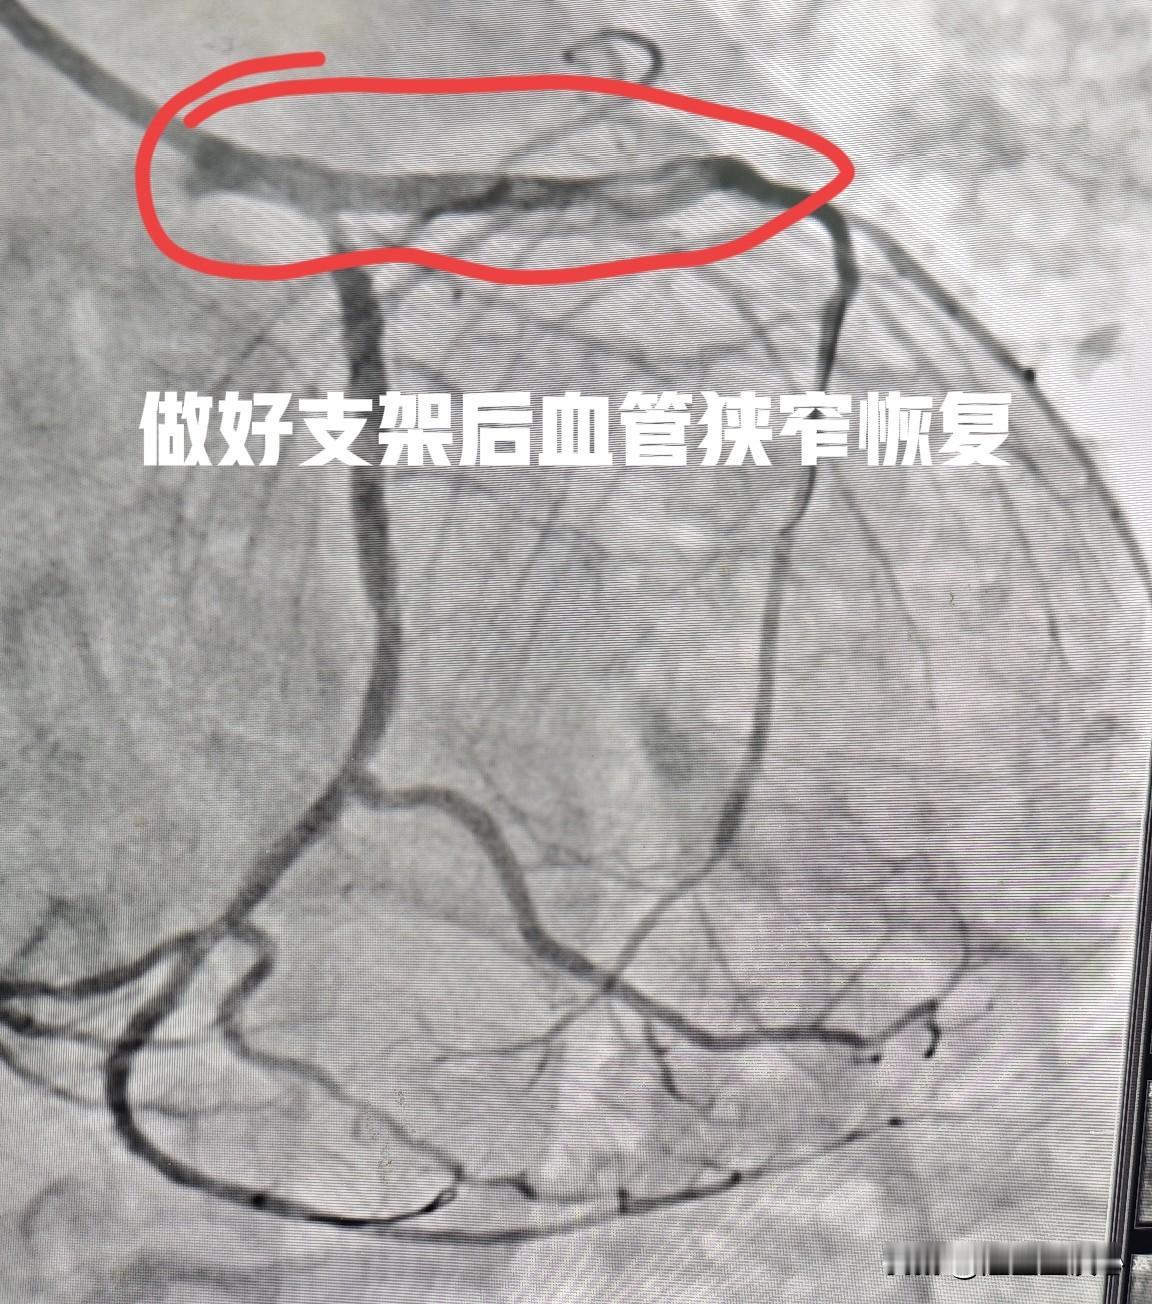

80 岁老人心脏支架手术中突发胸痛,一台风险又高又惊险的手术。80 岁老张平常没别的爱好,就是喜欢走走路,以往能走 3 公里多,最近 2 个星期走不到 500 米就气喘的不行。到当地医院检查发现心脏功能明显下降,射血分数下降到 32%(正常在 50-70%),相当于正常人心脏功能的一半。进一步冠脉造影发现,心脏血管的左主干至前降支开口、前降支近段严重钙化并重度狭窄。 这个患者手术的风险在于:第一,高龄。高龄老人身体各个器官功能都在退化,手术耐受性差。第二,血管狭窄位置特殊,位于左主干和前降支开口,操作过程中稍有不慎,会直接心脏停跳。第三,本身有严重心衰,手术过程中用的造影剂也会加重心衰。手术过程中也容易出现心脏骤停。 摆在老人面前其实很难选择,不手术心绞痛频繁出现,毫无生活质量,手术的话风险又太高。最后慎重决定,还是做手术。 手术过程中,果然担心的还是来了。血管狭窄太严重了,手术刚开始没一会,就开始频繁出现胸痛不适。心率也上窜下跳的,一会 110 次,一会突然降到 50 多次,血压也从 110 多垮到 80 多,不停地用各种血管活性药物维持,快速操作完成手术,好在有惊无险。 下一关就是术后恢复了。血管放支架 支架手术